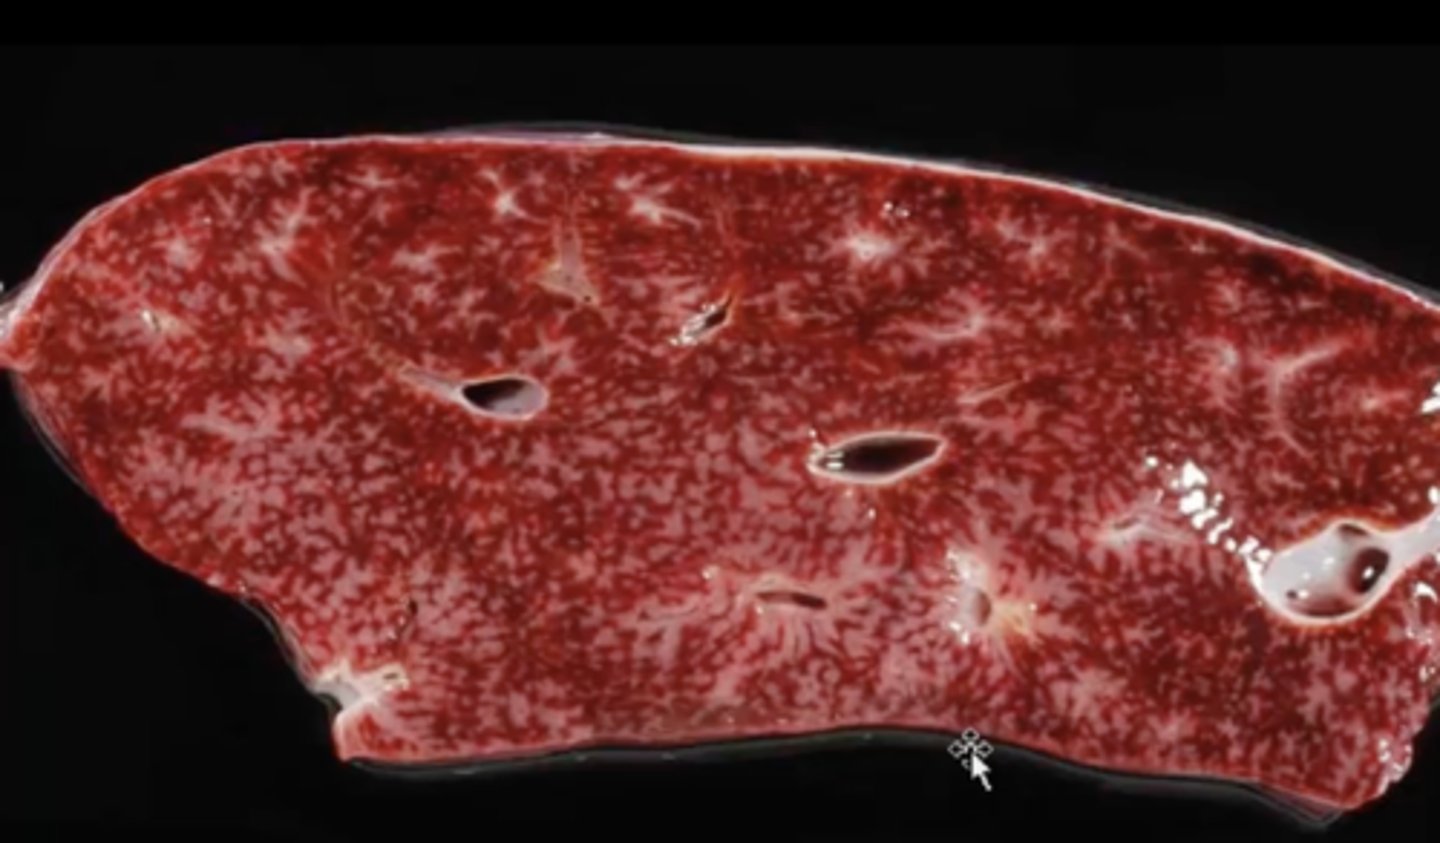

spleen, diffuse enlargement, rounded edges, mottled red color

splenomegaly - splenic lymphoma

Describe this lesion + diagnosis